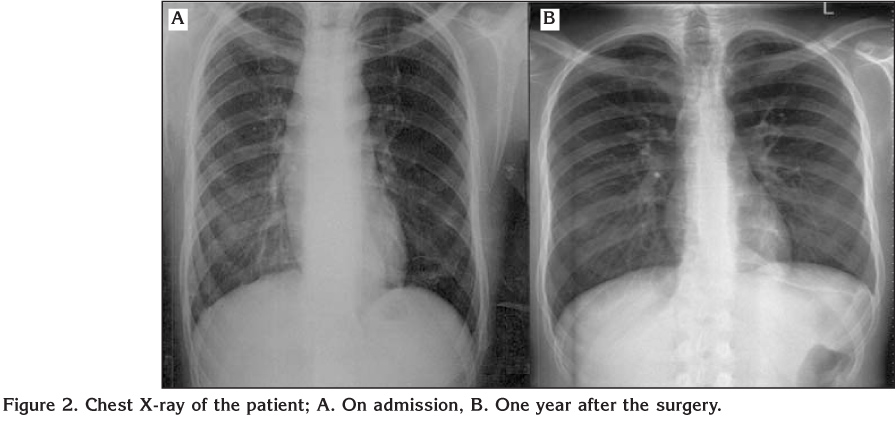

An 18-years-old male patient applied to a clinic with the complaints of cough, dyspnea, wheezing and diagnosed as asthma. A fluticasone/salmeterol combination inhaler therapy was prescribed. While he did not recover, inhaled steroid dosage was increased and montelukast was given as add-on-therapy. The patient was referred to our hospital with difficult asthma diagnosis. He reported cough increasing at night, regurgitation and dyspnea while eating. Spirometry revealed a non-reversible airway obstruction (Figure 1A). On chest X-ray there was a mild upper mediastinal enlargement (Figure 2A). Chest computed tomography revealed an over-dilated oesophagus constricting the trachea (Figure 3). The patient was referred to chest surgery clinic with a suspected diagnosis of achalasia. A clear narrowing of oesophagus at the oesophagogastric junction was seen in barium-oesophagogram (Figure 4). Oral intake was stopped and 3000 cc fluid was aspired with nasogastric tube. Endoscopic evaluation of the oesophagus revealed an increased pressure on lower oesophageal sphincter, dilated oesophagus without peristaltism. After left thoracotomy, increased pressure on lower oesophageal sphincter and dilated oesophagus was explored. The patient underwent Heller myotomy and oesophagogastrostomy. He was recovered in one week after the surgery without any complaint of dyspnea. Spirometry tests and chest X-ray resulted normal in one year (Figures 1B,1C,1D and Figure 2B).

Figure 2